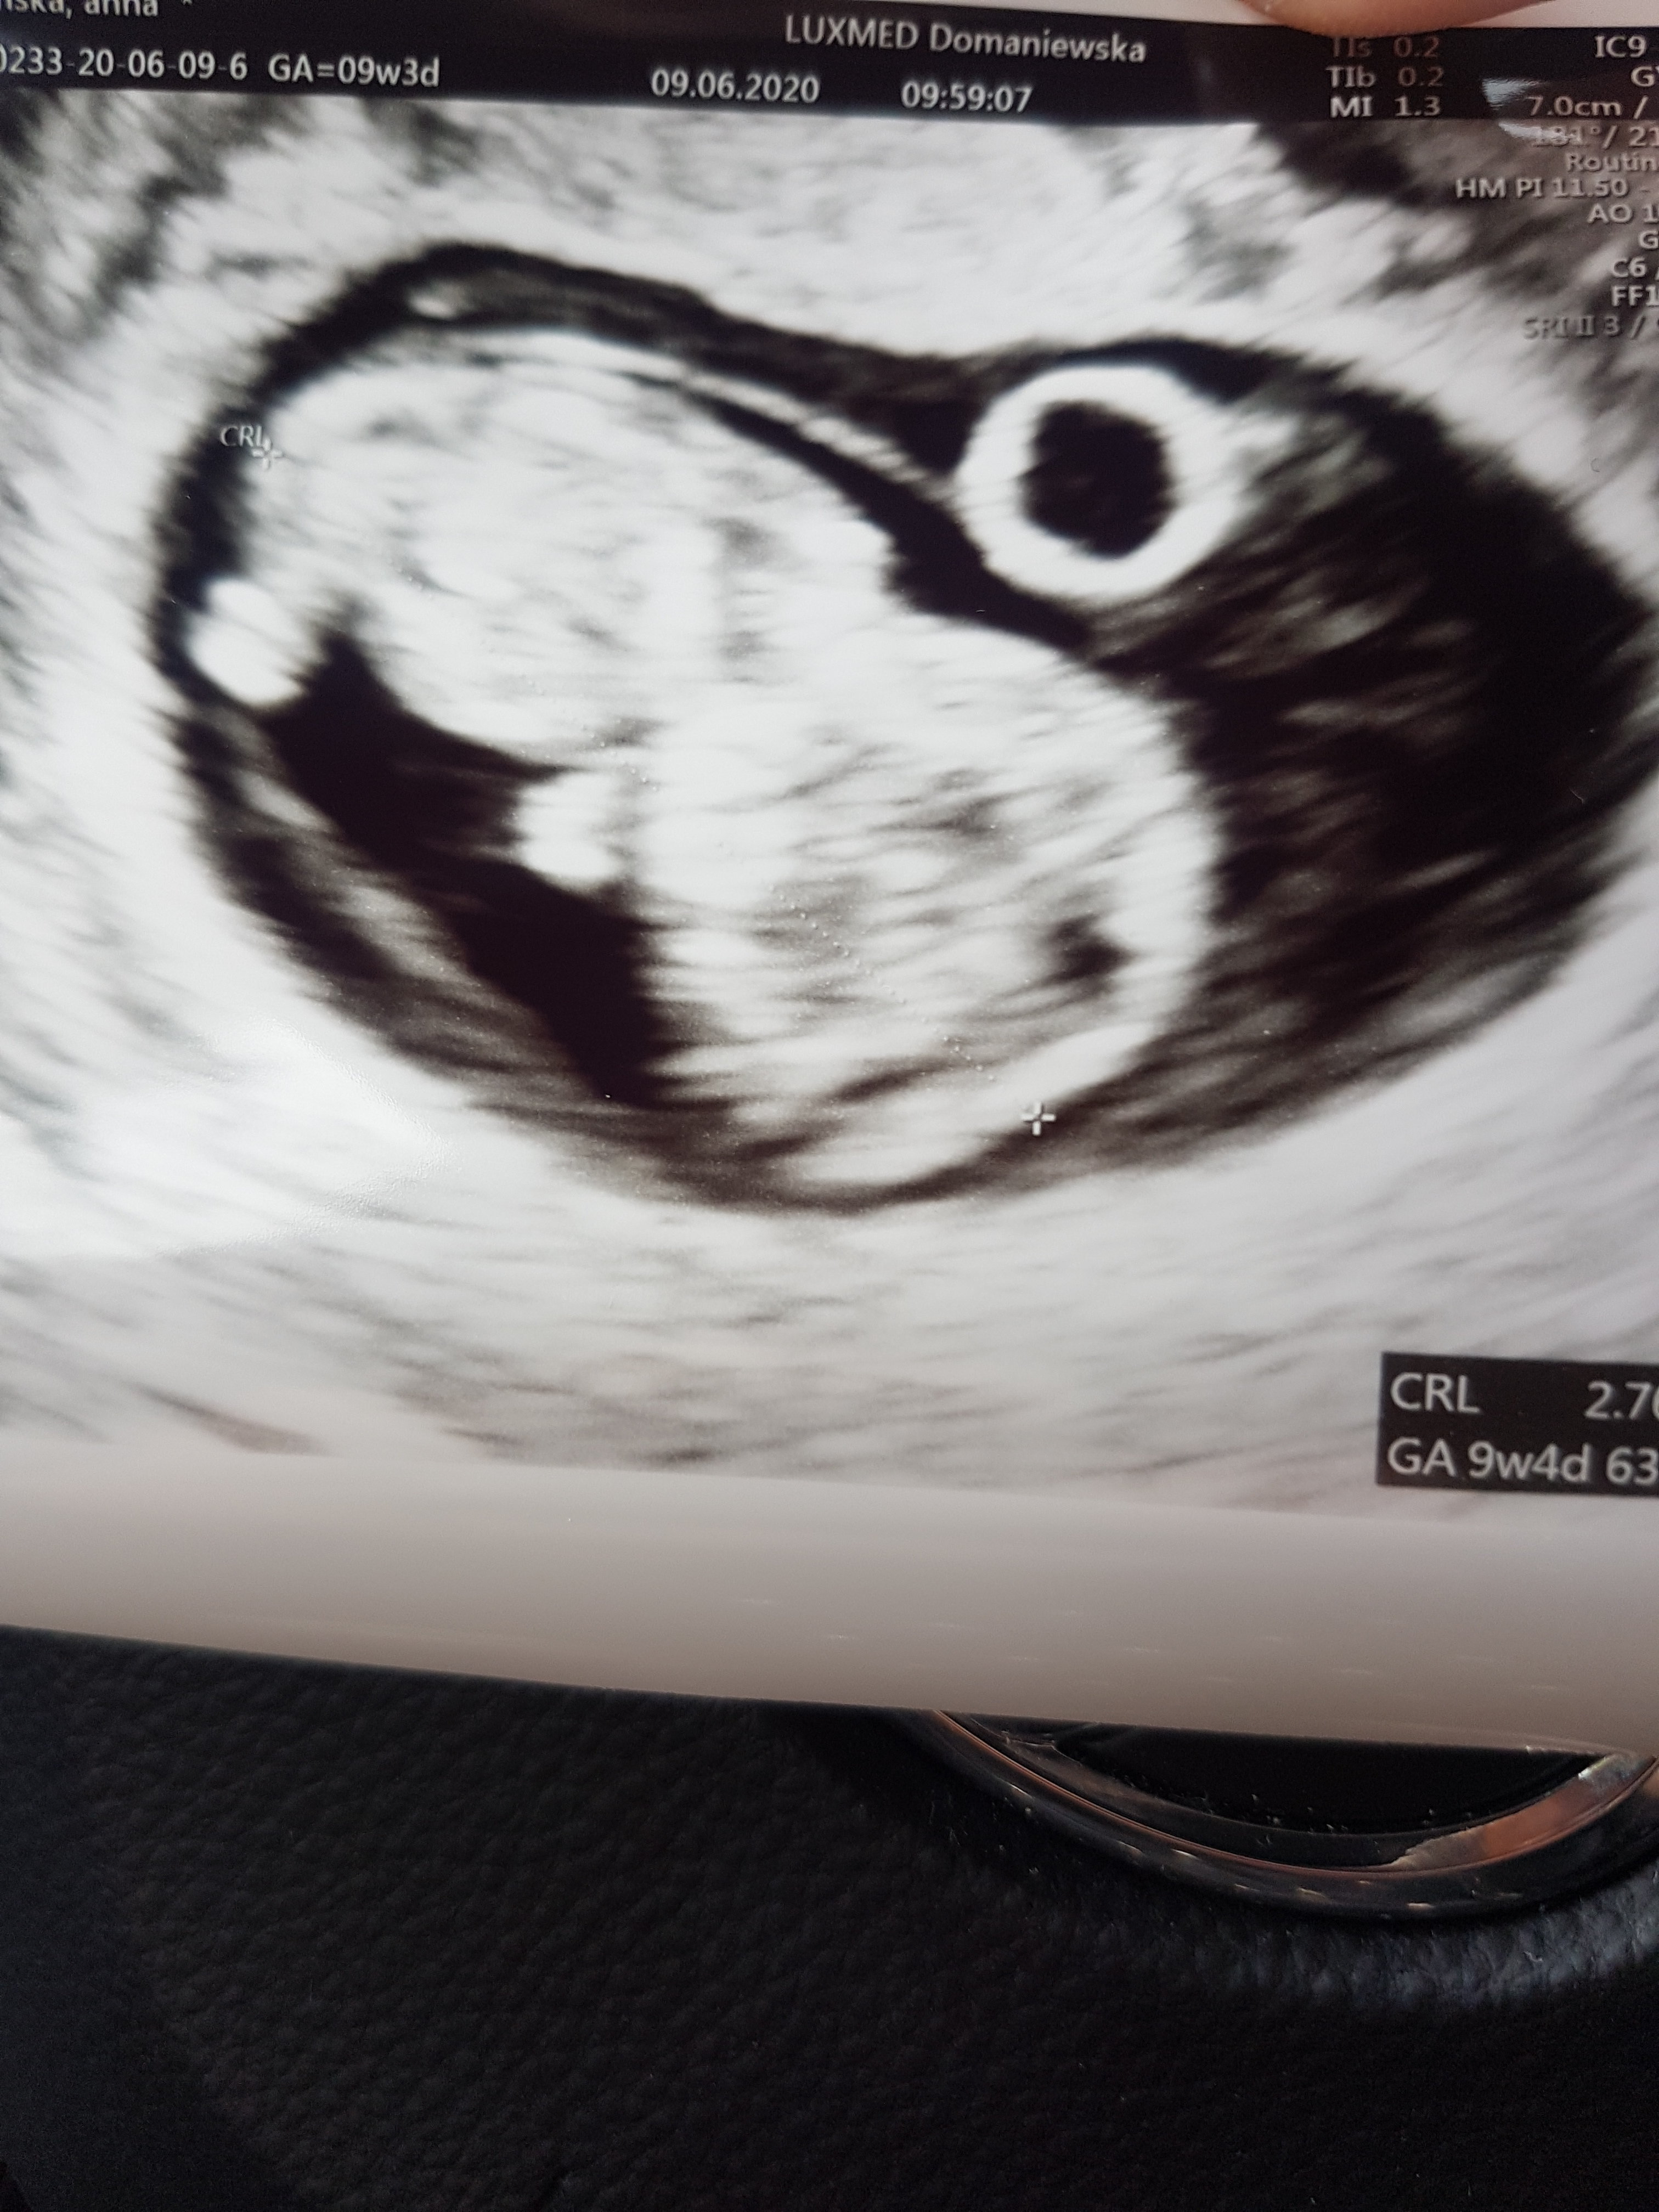

Ja już po badaniu . I bicie serduszka 140 na min

Załączniki

• 20200609_100729.jpg

20200609_100729.jpg

1,2 MB · Wyświetleń: 106